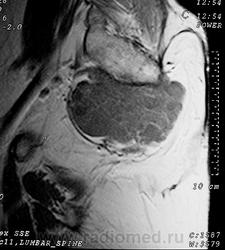

Сакральная хордома. Д-р Марсело Сенна Ксавье де Лима, Paul Roland Kaleff, и Антонио Рожерио del'Arco Roth Аугусто Варгас. Рецидив. Часть крестца была удалена ранее. Пнд, 27/11/2017 - 21:03 #1 Катенёв Валенти... Не на сайте Был на сайте: 7 лет 4 месяцев назад Зарегистрирован: 22.03.2008 - 22:15 Публикации: 54876 Внутричерепная хордома. http://pubs.rsna.org/doi/full/10.1148/rg.234025176 Пнд, 09/07/2018 - 20:44 #2 Катенёв Валенти... Не на сайте Был на сайте: 7 лет 4 месяцев назад Зарегистрирован: 22.03.2008 - 22:15 Публикации: 54876 Продолжение. Приложения: